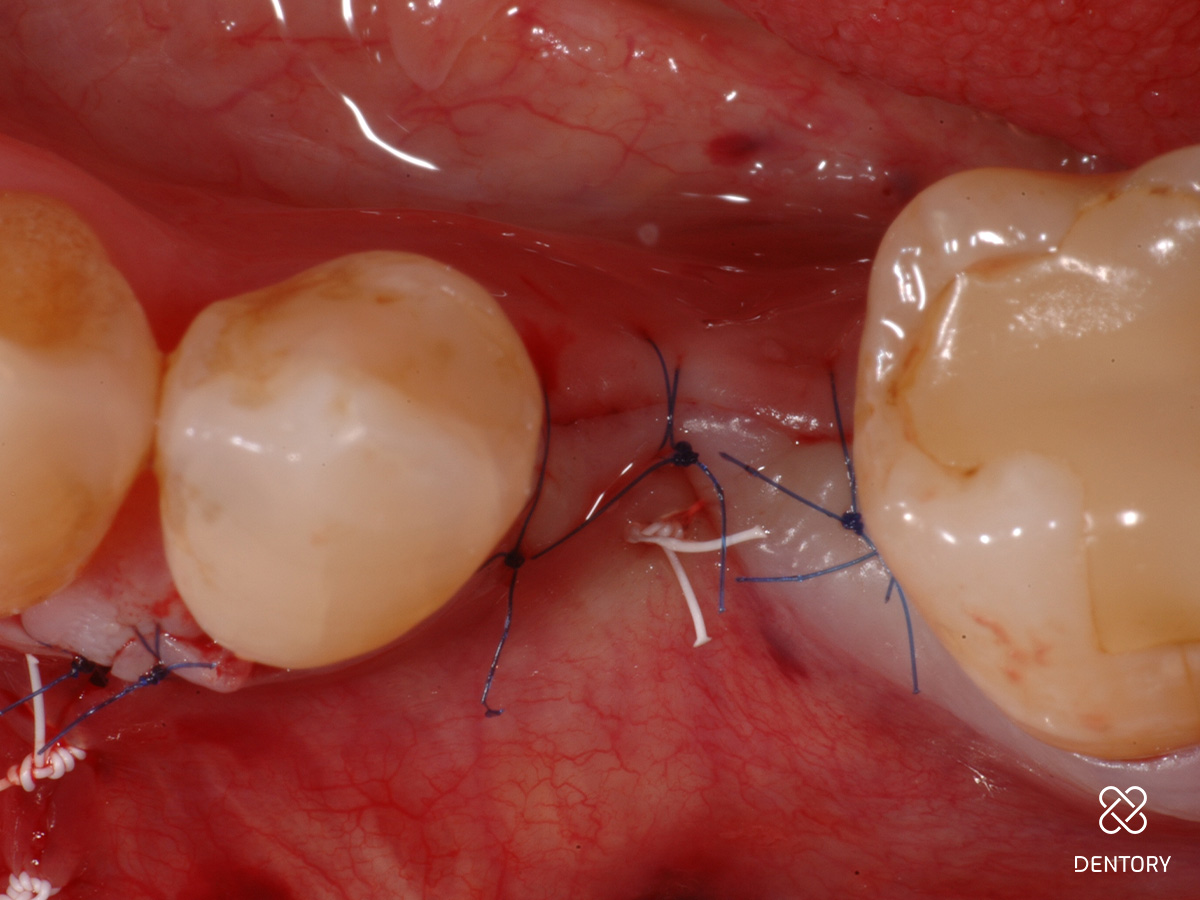

Abbildung 8

Nach Entlastung des Lappens durch Periostschlitzung erfolgt ein spannungsfreier, mehrschichtiger Nahtverschluss - die tiefe Komponente ist eine horizontale Matratzennaht (4-0 Keydent PTFE), darüber kommen sogenannte "Double-Sling-Sutures" (6-0 Seralene) zum liegen.